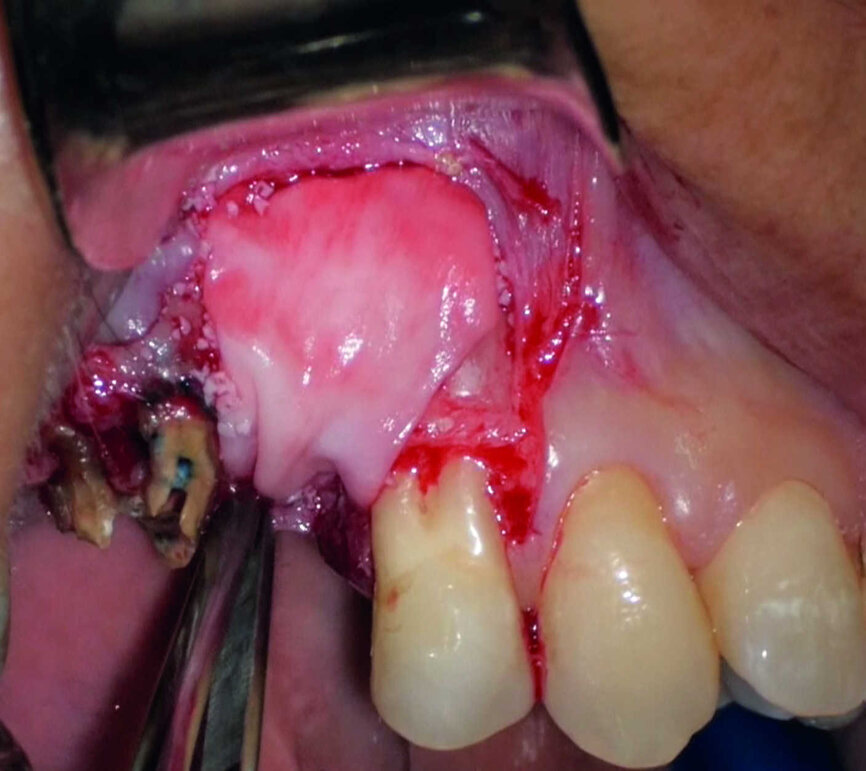

La comparaison des deux dents présentées dans les figures 10 à 22 démontre à quel point il importe d’analyser correctement toutes les coupes de l’examen CBCT. On peut voir que, dans la molaire maxillaire, la lésion commence sur la surface distale de la racine et pénètre dans la cavité pulpaire, mais s’arrête au tiers coronaire de la dent, sans affecter significativement l’intégrité du plancher de la cavité (Figs. 10–15). Les images cliniques illustrent les phases du traitement chirurgical, depuis le débridement de la résorption jusqu’à la restauration au moyen d’un ciment biocéramique (Figs. 16–19). Les clichés radiographiques finaux confirment le bien-fondé du traitement conservateur et endodontique de la dent. La situation est complètement différente pour la molaire mandibulaire, pour laquelle l’évaluation de l’examen CBCT révèle clairement l’étendue de la résorption, qui envahit le plancher de la cavité pulpaire jusqu’à la zone de furcation. Il serait impossible de détecter ce problème par le seul examen de la radiographie préopératoire (Figs. 20–22).

L’évaluation CBCT préopératoire est utile dans les cas nécessitant une approche chirurgicale, non seulement pour confirmer la présence d’une lésion, mais aussi pour planifier l’intervention et, en particulier, identifier le type d’incision chirurgicale à pratiquer, en fonction de la taille et de l’emplacement de la lésion en question (Figs. 23–25). Le cas spécifique présenté dans cet article est caractéristique de cette situation. La radiographie intraorale n’a pas permis de déterminer l’étendue de la lésion, qui touche non seulement la région apicale de la prémolaire, mais aussi un segment édenté en distal. Cette région doit faire l’objet d’un traitement régénérateur, afin de garantir la cicatrisation appropriée de la zone, suivi par la mise en place d’une membrane. Une approche totalement différente de celle requise pour la chirurgie endodontique doit être utilisée pour protéger le lambeau. Les différentes étapes de l’intervention sont illustrées dans les images peropératoires (Figs. 26–28). L’examen CBCT réalisé 12 mois plus tard, confirme la cicatrisation complète de la lésion apicale et la parfaite intégration de la greffe (Figs. 29–31).